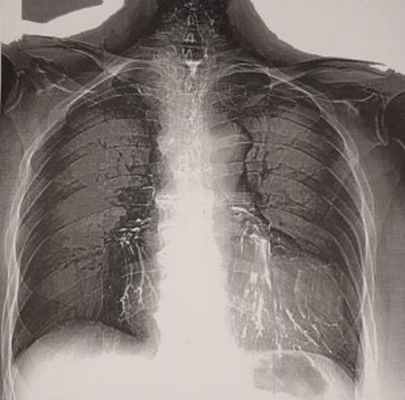

К 9 суткам, сознание - 5 баллов, взгляд не фиксирует, не следит, расходящееся косоглазие. Спустя 2 недели после полученных травм на компьютерной томографии органов грудной клетки выявлены признаки правосторонней гиповентиляционной пневмонии.

Лучевое исследование включает выполнение рентгеноскопии и рентгенографии легких, эзофагографии, МСКТ грудной клетки. Контрастное исследование пищевода проводят очень осторожно, используя водорастворимые или масляные вещества, которые вводятся через зонд (применение сульфата бария в этих случаях недопустимо). Трахеопищеводный свищ требует проведения тщательной дифференциальной диагностики с изолированной атрезией и стенозом пищевода, гастроэзофагеальным рефлюксом, ахалазией кардии, дисфагией различного генеза.

- Обязательным является проведение рентгенографии и рентгеноскопии пищевода с водорастворимым контрастным веществом (барий использовать не рекомендуется, рисунок 1, 2).

Рисунок 2. Остатки бария сульфата в бронхах у пациентки с пищеводно-бронхиальными свищами